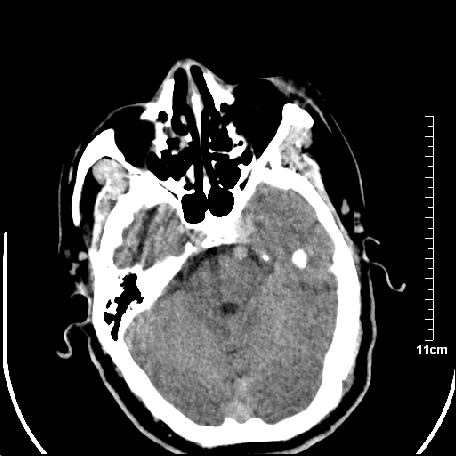

外伤患者,什么病,

外伤患者,没什么症状,

颅内未见明显创伤性影像,建议上传骨窗,看看左侧颧弓

双侧外侧裂,左侧脑沟见高密度结节影,边清,还有鞍上池层面密度也高

2.老年脑,基底动脉硬化迂曲。

基底动脉硬化迂曲。高血红蛋白血症。